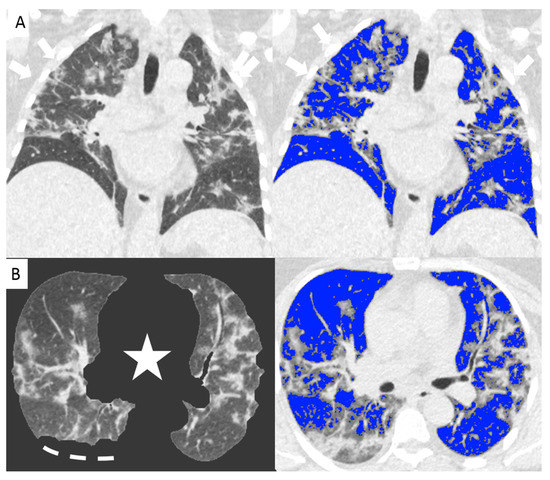

Since the beginning of the Covid-19 outbreak certain diagnosis of the disease was complicated by the multiplicity of symptoms and imaging features and due to the variability in the severity of disease at the time of presentation [1]. Chest CT has demonstrated an important role in predicting patients’ outcome because of the correlations between CT features and the severity of the disease [7,13]. In our study we demonstrated the correlation between the lung volume affected by the COVID-19 pneumonia and clinical outcome with a direct relationship between the infected lung percentage and the need for ventilation or subsequent death. Figure 2 and Figure 3 show lung volume analysis with dedicated software in comparison with standard CT images.

Figure 2. Non-enhanced coronal reconstructions of Chest CT (A), (upper panel) showing bilateral ground glass opacities with random distribution and consolidations in the upper and lower lobes (arrows). Lower panel show axial CT reconstructions of the same patient with automatic software segmentation (B) excluding all “non-lung” structures, (star) and not evaluable parenchyma due to pleural effusion (segmented line). Images on the right show software evaluation of the well aerated lung (blue) and the infected parenchyma (grey zone, arrows) discriminated by specific threshold. The whole infected volume assessed by software was 47% of the entire lung volume. The patient underwent invasive ventilation.